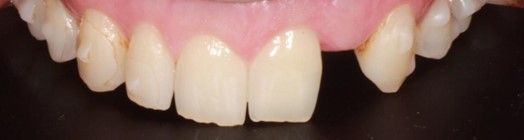

Tras 4 meses de la colocación del implante de circona y la corona provisional (Figura 12), se procedió al escaneado intraoral del muñón para la confección de una corona de circona monolítica.

La corona fue preparada mediante un protocolo adhesivo mecanoquímico18,19, que consistió en el arenado con partículas de óxido de aluminio de 30µm y la aplicación de un adhesivo universal con 10-MDP (Scotchbond Universal, 3M Espe, 3M, Saint Paul, Minnesota, USA). Con seda dental se comprobaron los puntos de contacto y la oclusión fue comprobada con papel de articular de 12 y 8 μm, para asegurar la ausencia de contactos prematuros, así como un correcto contacto anterior. A continuación, se procedió a cementarla mediante un cemento de resina dual (RelyX Unicem 2, 3M Espe, 3M, Saint Paul, Minnesota, USA). Se polimerizó durante 2 segundos con una lámpara de fotopolimerización, se retiraron los excesos mediante hilo dental y sonda, procediéndose a fotopolimerizar durante 40 segundos más en cada cara de la corona. El paciente expresó su satisfacción con el tratamiento a nivel estético y funcional, con un seguimiento clínico de 12 meses (Figura 13).